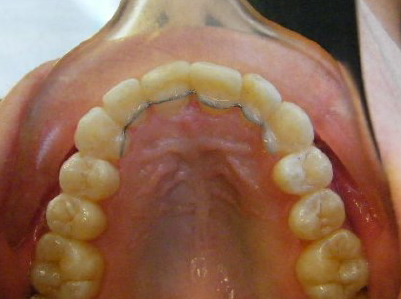

Patient 1: Severe upper and lower crowding with congenitally missing two lower adult teeth and a crossbite.